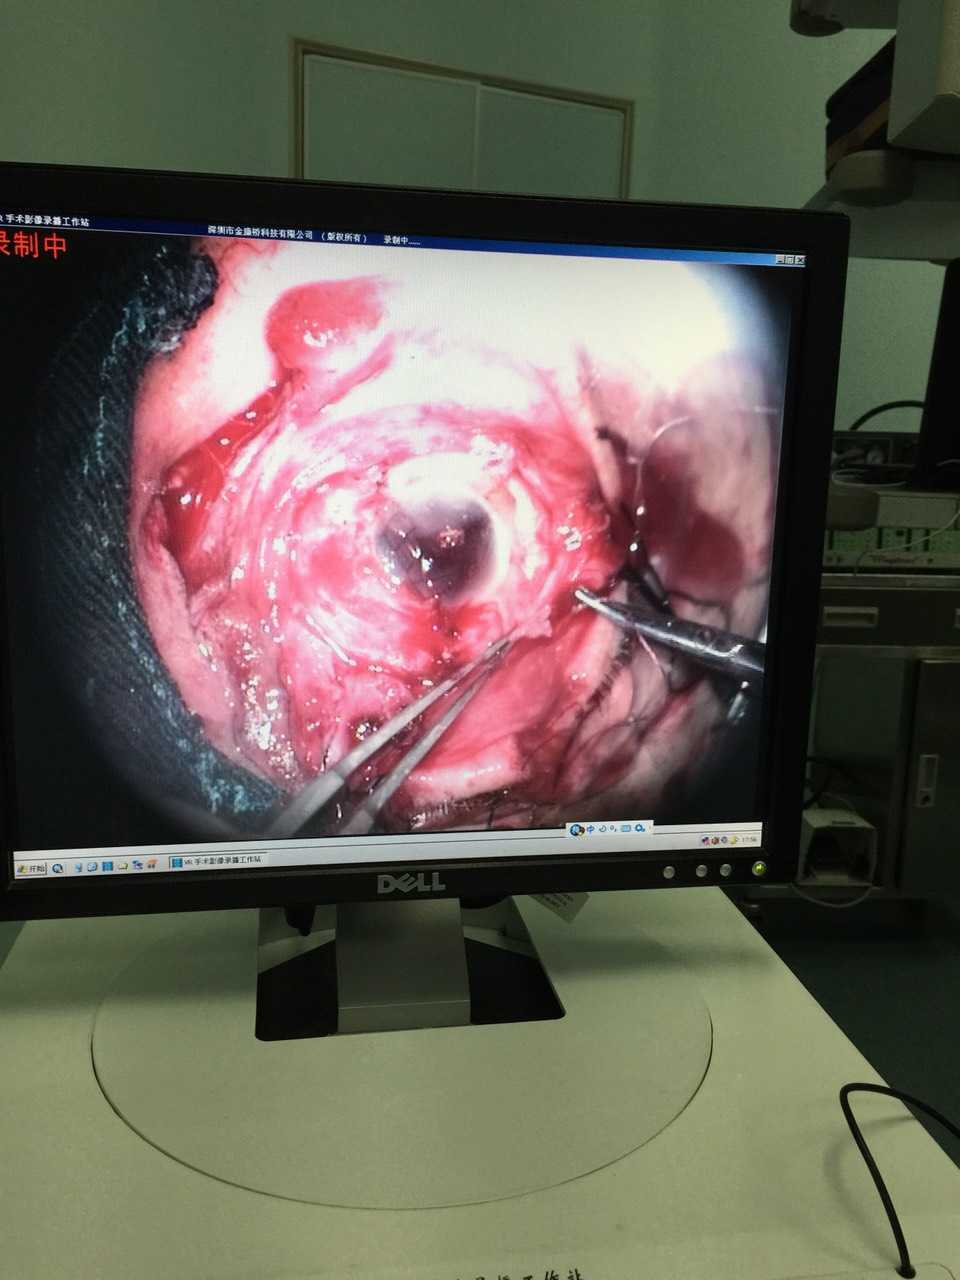

眼科胡莲娜主任:猴年的第一台眼科手术,即为*花爆烟竹**所致眼球破裂伤,患者50岁,除夕夜带家人放花炮,在点燃烟花的瞬间发生爆燃导致右眼上睑全层裂伤,上下泪小管断裂,眼球破裂,眶内壁骨折。在当地医院做了简单的处理,因为病情太复杂,于今日中午12:00转来我院。

经过必要的检查和评估,下午3点,手术在全麻下开始进行。由于患者面部肿胀口周干裂而张口受限,麻醉插管及其困难,麻醉师梁庆伟想尽一切办法使插管成功,保证了手术顺利进行。

患者眼球破碎的实在厉害,我和高付林主任、赵宏伟医生经过3个小时的手术,终于将破裂严重的眼球恢复了基本形态。紧接着又开始修复眼睑和泪小管。

虽然泪道引流管插管顺利,但由于患者鼻中隔偏曲加上鼻粘膜肿胀,采用传统方法根本无法将引流管自下鼻道引出。于是紧急求助耳鼻喉科周莹医生前来支援,在鼻腔内窥镜辅助下,经过多次收缩鼻粘膜,最终将引流管顺利引出,最后在显微镜下吻合上下泪小管。

虽然我们暂时保住了患者的眼球,但他这只眼将永远失去光明。所以朋友们,来路不明的*花爆烟竹**千万不能买,燃放*花爆烟竹**一定注意安全防范。